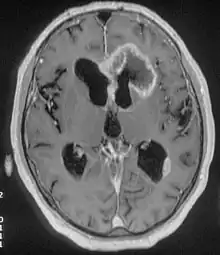

There are many different causes of frontal lobe epilepsy ranging from genetics to head trauma that result in lesions in the frontal lobes.[4] Although frontal lobe epilepsy is often misdiagnosed, tests such as prolonged EEG monitoring, video EEG and/or an MRI scan of the frontal lobes can be administered in order to reveal the presence of a tumor or vascular malformation.[4] Unlike most epileptic EEGs, the abnormalities in FLE EEGs precede the physical onset of the seizure and aid in localization of the seizure's origin.[4] Medications such as anti-epileptic drugs can typically control the onset of seizures, however, if medications are ineffective the patient may undergo surgery to have focal areas of the frontal lobe removed.[4]

Neuroimaging for diagnosis

Advancements in technology, has given rise to newer, more efficient methods of diagnosis, most prominent being in the domain of neuroimaging.[7] The high spatial resolution from fMRI has implications on certain brain regions contributing to memory.[7] The usage of task fMRI for examination of memory or other higher cognitive networks may also be used to predict ictal onset zone(s) in patients with FLE, giving the advantage of refinement of patient-specific analyses.[7] The use of multi-modal approaches in association with neuroimaging techniques like fMRI and MEG or EEG will be informative in characterizing atypical functional brain networks in FLE.[7] But, difficulty remains in the evaluation of potential compensatory mechanisms between patients with FLE with normal and impaired memory, without properly characterizing transfer of information during memory tasks.[7]